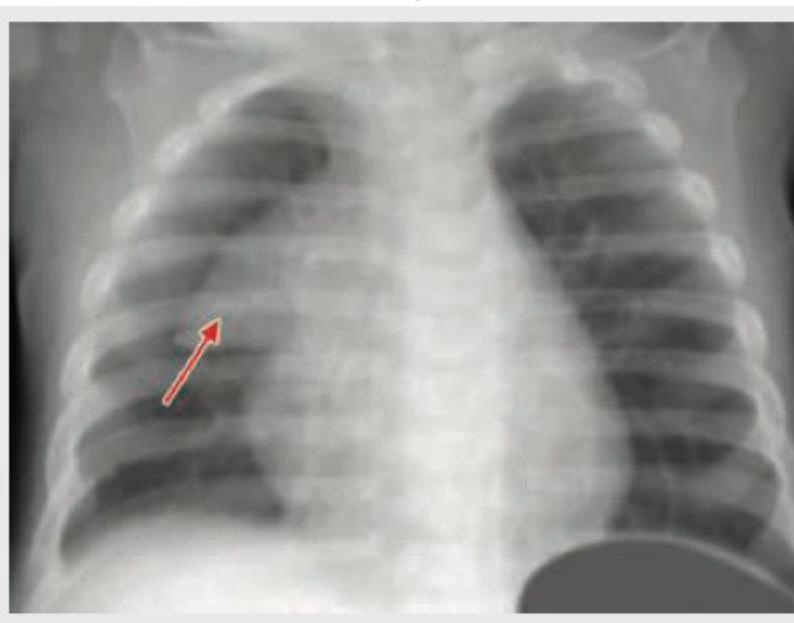

Comment on the arrow marked structure in CXR of an infant: (Recent NEET Pattern 2018-19)

Explanation: ***Sail sign*** - The arrow points to an elevated, well-defined triangular shadow in the right upper mediastinum, characteristic of the **thymus gland** in an infant. - This appearance is known as the **"sail sign"** due to its resemblance to a boat's sail, caused by the normal shape of the thymus in young children. *Lingular lobe pneumonia* - Lingular lobe pneumonia would appear as an **area of consolidation** or opacification, usually in the left mid-to-lower lung field, which is not depicted here. - This pathology typically results in a loss of the normal markings of the lung parenchyma, unlike the clear outline seen in the image. *Pneumothorax* - A pneumothorax would present as a **collection of air** in the pleural space, characterized by the absence of lung markings in the affected area and a visible visceral pleural line. - There is no evidence of displaced lung tissue, collapsed lung, or an abnormal air collection in the image. *Dextrocardia* - Dextrocardia refers to a condition where the **heart is located on the right side** of the chest. - In this image, the cardiac silhouette is clearly on the left side, indicating a normally positioned heart.